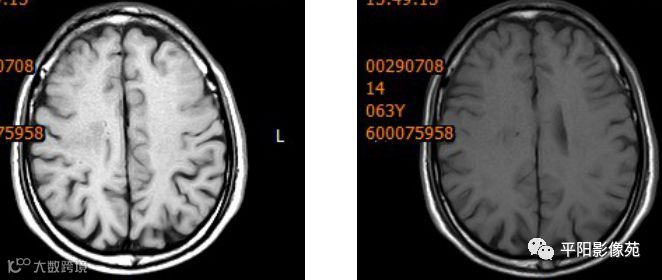

右侧额叶中央前回局部脑裂增宽,并向内延伸,周围衬以等灰质信号,呈稍长T1稍长T2信号,病灶自软脑膜向内延伸,与室管膜相连。